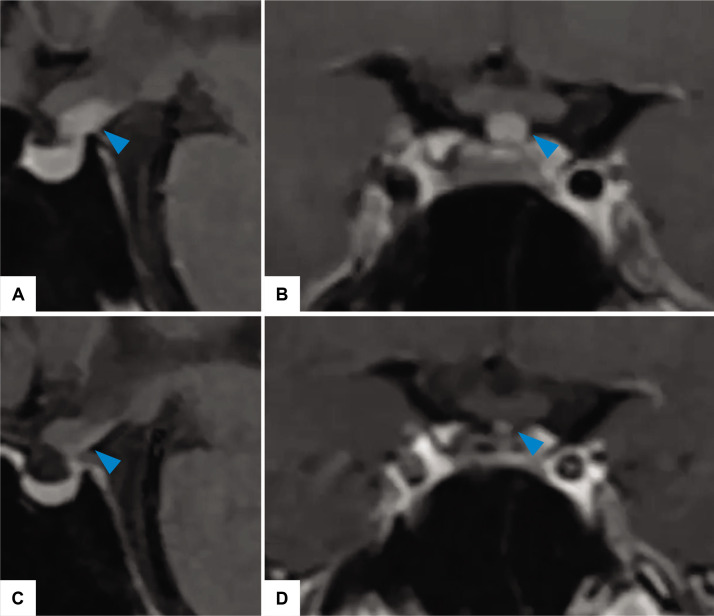

Lymphocytic hypophysitis (LHy) is a rare autoimmune inflammatory process that selectively affects the neurohypophysis and infundibulum, typically presenting with arginine vasopressin deficiency (AVP-D). On magnetic resonance imaging (MRI) with contrast, there is a thickening of the pituitary stalk, enlargement of the neurohypophysis or both with homogeneous enhancement. LHy can be self-limiting and regression can be seen radiologically during follow-up. A 22-year-old male presented with clinical findings consistent with AVP-D in 2016. MRI brain demonstrated enlargement of the pituitary stalk and absence of a posterior pituitary bright spot. He was given a trial of glucocorticoid treatment. His serial MRI brain showed a reduction of the pituitary stalk, but the AVP-D persisted. He was diagnosed with LHy. LHy is characterized by lymphocytic infiltration, leading to eventual destruction of the pituitary tissue accompanied by varying degrees of pituitary dysfunction. Definite diagnosis can only be established via pituitary stalk biopsy. Due to the wide range of possible aetiologies, close monitoring is strongly recommended for the treatment of presumed cases lacking histopathologic confirmation. The response rate to glucocorticoids has been variable. Periodic monitoring of anterior pituitary function and pituitary MRI are essential in the management of this condition.